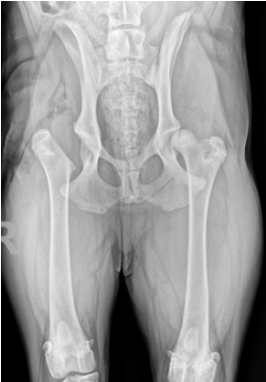

This patient has had bilateral total hip replacements. Each side is a separate surgery, generally staged several months apart.